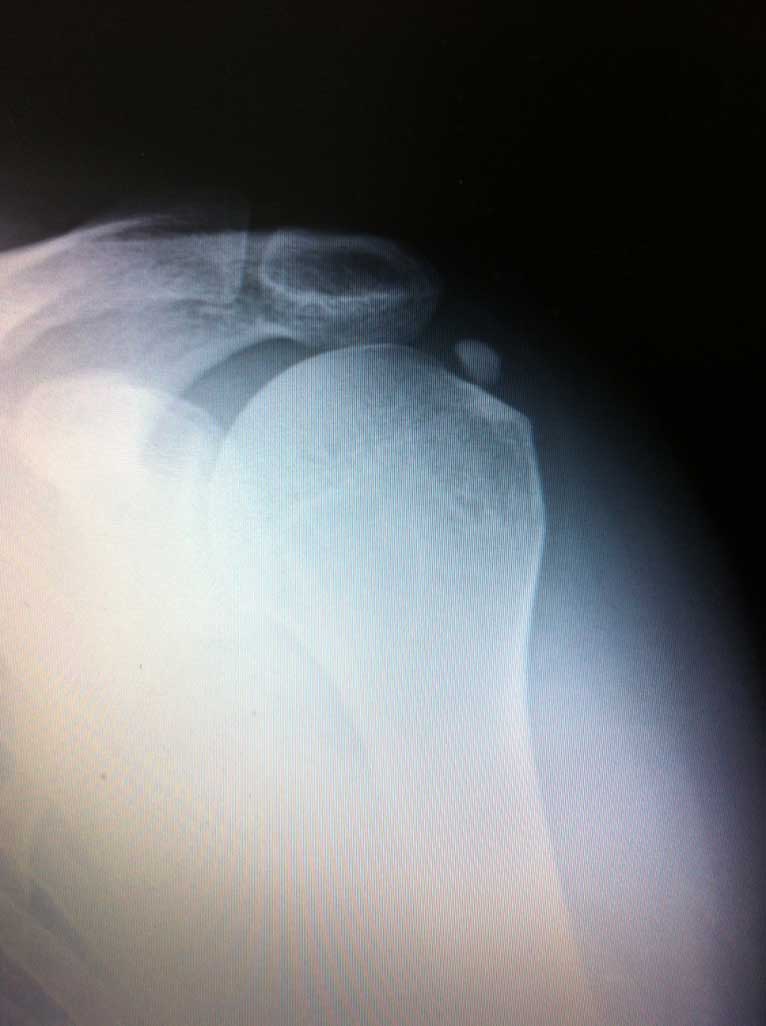

Das eigentliche Schultergelenk besteht aus 2 knöchernen Partnern, dem Oberarmkopf und der Gelenkpfanne, welche ein Teil des Schulterblattes ist. Dank der sehr flachen und eher kleinen Pfanne und wesentlich grösserem Kopf ermöglich die knöcherne Zusammensetzung des Gelenkes ein sehr grosses Bewegungsausmaß desselben.

Wie auf der Bilddokumentation ersichtlich, wird die Kontaktfläche zwischen der kleinen knöchernen Pfanne und dem Kopf durch einen knorpeligen Ring, s.g. Labrum, der sich am Pfannenrand befindet, vergrössert.

Ähnlich wie in anderen Gelenken, sorgen auch in der Schulter die s.g. passiven und aktiven Stabilisatoren für das Zusammenhalten der zwei o.g. knöchernen Gelenkpartnern ( Kopf und Pfanne ).